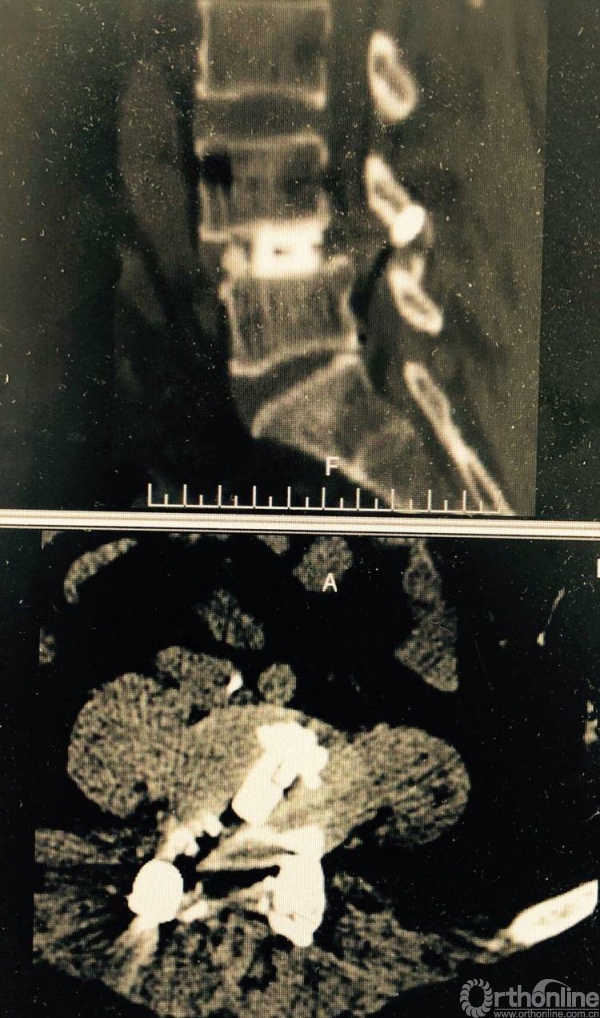

术前CT示L4/5重度椎管狭窄,腰椎滑脱合并硬膜囊受压。辅助检查如下:

术前CT